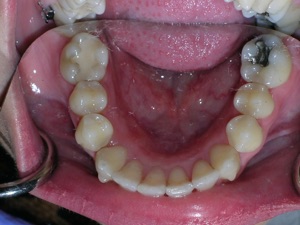

Here are some progress photos.

And more.